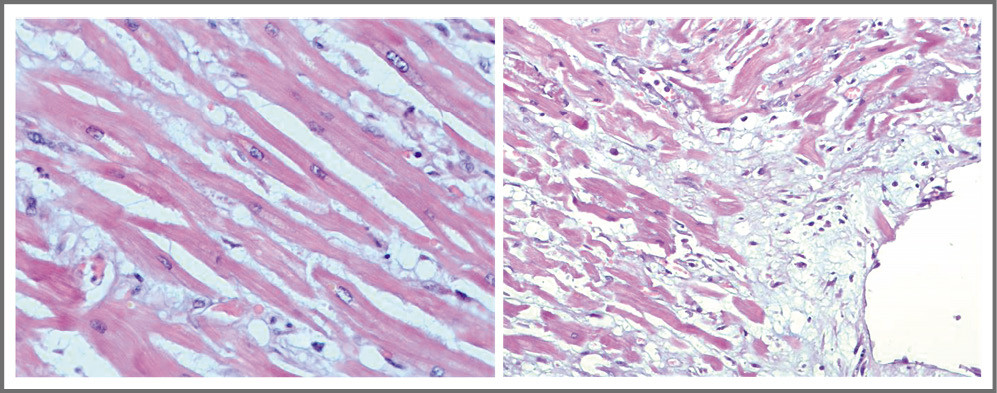

При проведении патологоанатомического исследования выявлен выраженный отек стромы миокарда с воспалительной лимфоцитарной инфильтрацией. Гистологическая картина соответствовала иммунологическим критериям острого миокардита (≥14 лейкоцитов/мм2, включая до 4 моноцитов/мм2, при наличии CD3-положительных Т-лимфоцитов в количестве ≥7 клеток на мм2) и далласским критериям миокардита (рис. 5). Помимо этого выявлена полисегментарная пневмония в стадии организации.

Рис. 5. Значительный отек стромы миокарда, лейкоцитарная инфильтрация.